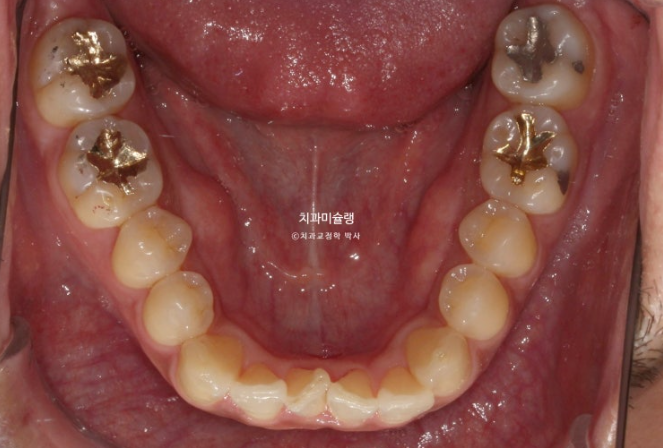

덧니가 있고 위아래 치아 중심선이 어긋나 있습니다.

치아중심선이 어긋나 있는 것은 아래턱 비대칭이 있기 때문입니다.

그러나 사랑니 공간이 없는 상황이라 비발치 후방이동 방법은 쓰기 어렵습니다.

따라서 상악 악궁확장장치를 통해 덧니를 해결하기로 합니다.

30대 후반이라는 나이와 성별을 고려하면 악궁확장 실패 가능성이 커서 악궁확장장치 심는 날 봉합부를 따라 뼈를 느슨하게 만드는 corticopuncture도 함께 시행해야 합니다.